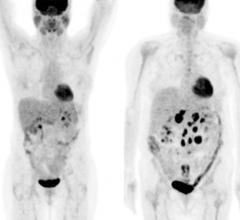

Positron emission tomography (PET) is a nuclear imaging technology (also referred to as molecular imaging) that enables visualization of metabolic processes in the body. The basics of PET imaging is that the technique detects pairs of gamma rays emitted indirectly by a positron-emitting radionuclide (also called radiopharmaceuticals, radionuclides or radiotracer). The tracer is injected into a vein on a biologically active molecule, usually a sugar that is used for cellular energy. PET systems have sensitive detector panels to capture gamma ray emissions from inside the body and use software to plot to triangulate the source of the emissions, creating 3-D computed tomography images of the tracer concentrations within the body.